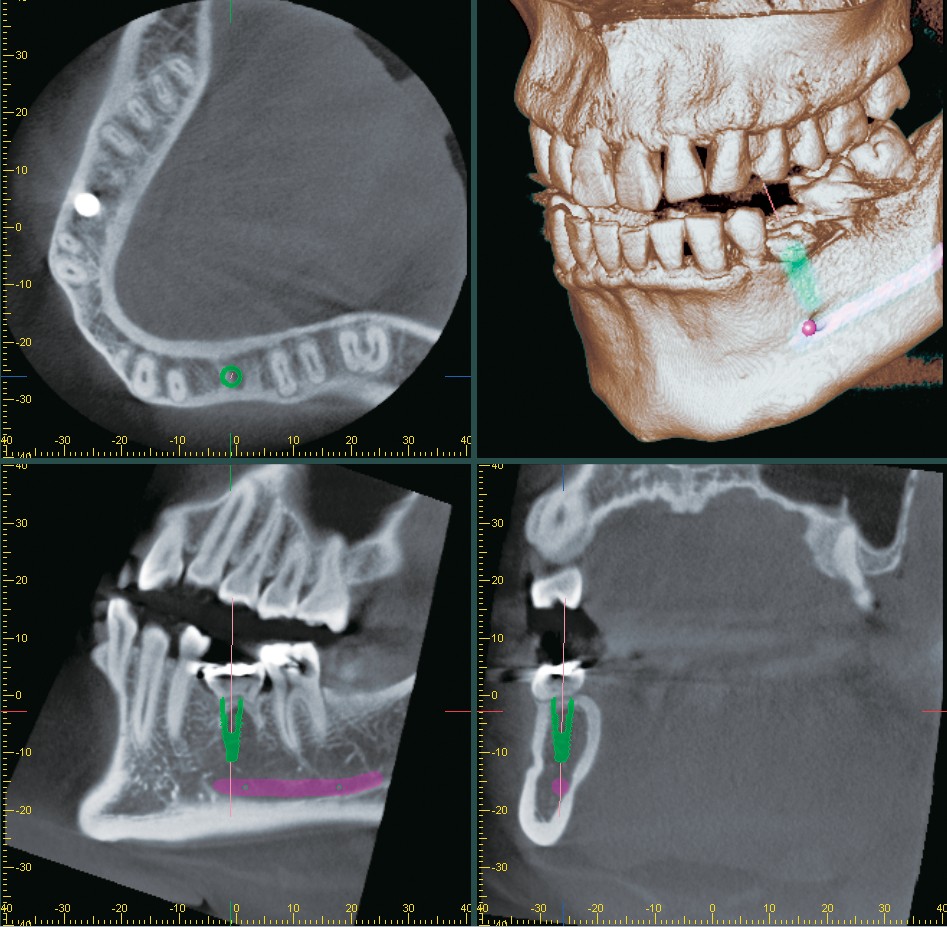

Morita i-Dixel imaging software presents a wide variety of services to its users ensuring they reach an accurate

diagnosis for their cases. The software features a drawing function, presentations for implant therapy, and the

ability to convert three-dimensional x-rays to solid images to allow for rotation, magnification, and slicing of the

image. i-Dixel also boasts a unique feature, which is the ability to view both CT slice images and volumerendered images simultaneously on the computer screen. It is compatible with DICOM 3.0 and ensures